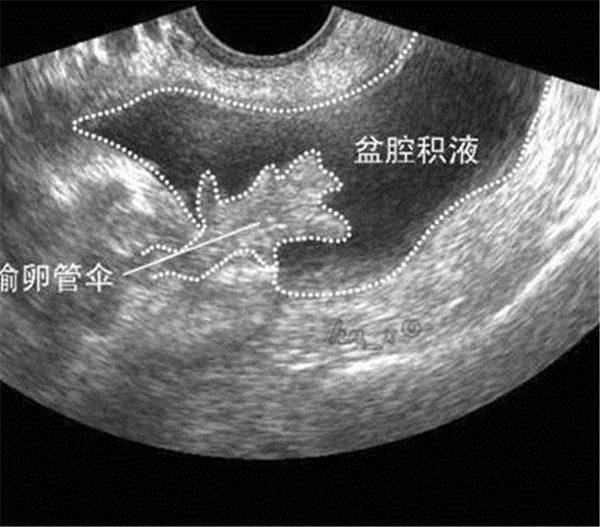

2、宫腔积血、积脓、积液

(宫腔积液)